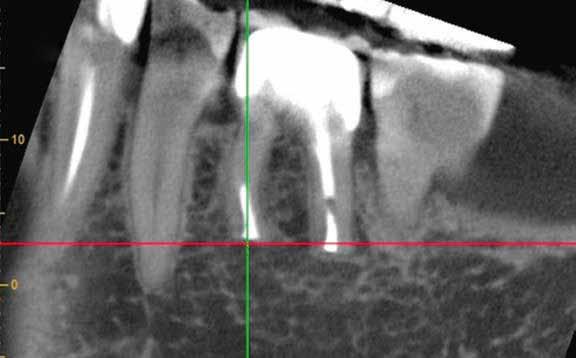

1. a-n. ábrák: Preoperatív CBCT-felvétel a bal alsó 6-os (3.6) fogról. Az axialis (a), coronalis (b) és sagittalis (c) nézeteken a mezialis és distalis gyökerek apicalis harmada körül sugáráteresztő zóna és ép buccalis corticalis csont látható. Egy olyan sablont terveztünk, amely jelezte a csontablak határait az apicalis terület pontos elérése érdekében (d). A mikrosebészeti bevatkozás során a sablont a helyére illesztettük (e), a csontablak határait megjelöltük (f) egy Piezotome CUBE LED kézi-darabba fogott fűrésszel, majd kivágtuk és eltávolítottuk (g és h) az apicalis területhez történő hozzáférés, illetve a mezialis és distalis gyökerek rezekciójának, retrográd preparációjának és retrográd gyökértömésének elvégzése érdekében (i). Végezetül a csontablakot visszaillesztettük és kollagén szivaccsal stabilizáltuk (j). A műtét után közvetlenül készített röntgenfelvétel a 3.6-os fogról (k). A kétéves kontroll során készített CBCT-felvétel: axialis (l), coronalis (m) és sagittalis (n) nézetek.

Klinikai vizsgálat során vertikális kopogtatási érzékenységet jelzett. A fog körül mérhető szondázási mélység és a fogmobilitás fiziológiás volt. A CBCT-felvételen nem észleltünk a csontos regeneráció megindulására utaló jeleket (1. a–c. ábrák). A korábban gyökérkezelt, gyökértömött és revideált 3.6-os fog esetében az alábbi diagnózis került felállításra: periodontitis periapicalis symptomatica. A panaszokat okozó fog további ellátása során navigált endodonciai mikrosebészetet kívántunk alkalmazni. Az alsó állcsontról intraorális szkent (TRIOS, 3Shape) készítettünk, és a felszíni topográfiát tartalmazó STL fájlt, valamint a CBCT-felvétel készítése során nyert DICOM fájlokat a Blue Sky Bio szoftver segítségével egyesítettük. A sebészi sablon megtervezésére az így kapott háromdimenziós képet használtuk. A sablon kialakítása során arra törekedtünk, hogy a sablon egyértelműen meghatározza a gyökércsúcsi terület eléréséhez szükséges csontablak határait (1. d. ábra)

A beavatkozás során helyi érzéstelenítésben teljes vastagságú mucoperiostealis lebenyt képeztünk, és a sablon segítségével bejelöltük a preparálandó csontablak határait. Az ablak széleinek megfelelően Piezotome CUBE LED kézi-darabbal (ACTEON) a kortikális teljes vastagságában vágást ejtettünk, majd az így kapott csontlemezt (ablakot) eltávolítottuk (1. e–h. ábra), és ezt követően steril fiziológiás sóoldatba helyeztük. A rezekció elvégzését követően (1. i. ábra) a mezialis csatornákat ultrahangos eszközök segítségével (NSK) retrográd irányból preparáltuk, majd az így kialakított mélyedésbe retrográd gyökértömést készítettünk. A tömés anyagául az EndoSequence BC RRM Fast Set Putty-t (Brasseler) választottuk. A tömés elkészítését követően a csontablakot visszaillesztettük, és a stabilizálása érdekében a vágásoknak megfelelően kialakult résekbe kollagén szivacsokat (Collagen Tape, Zimmer Biomet) helyeztünk (1. j-k. ábra). A lebenyt 6/0-s Prolene varratokkal (Corpaul) rögzítettük.

A kétéves kontroll során elvégzett klinikai és radiológiai vizsgálat (CBCT-felvétel) a periapicalis elváltozások megszűnését és a corticalis csontállomány tünet- és szövődménymentes gyógyulását